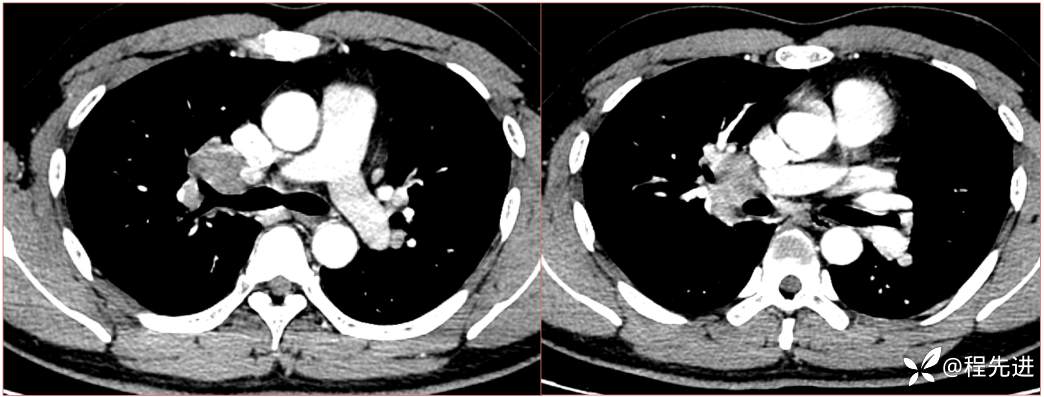

2023国庆特别精彩病例(一)|阵发性刺激性咳嗽,咳少量白色粘液痰1周|结果已公布

患者年龄:34岁

简要病史:患者一周前无明显诱因出现阵发性刺激性咳嗽,咳少量白色粘液痰,咳嗽无明显昼夜节律性,无发热、畏冷、寒战,无头痛、胸闷、胸痛,自行服药后 (具体不详) 症状无缓解,3天前外院胸片检查示右上病变

辅助检查:肺肿瘤标志物:神经元特异性烯醇化酶(NSE):35.72ng/ml(参考值0-16.3);非小细胞肺癌相关抗原211、胚抗原糖类抗原125、铁蛋白、鳞状细胞癌抗原未见异常